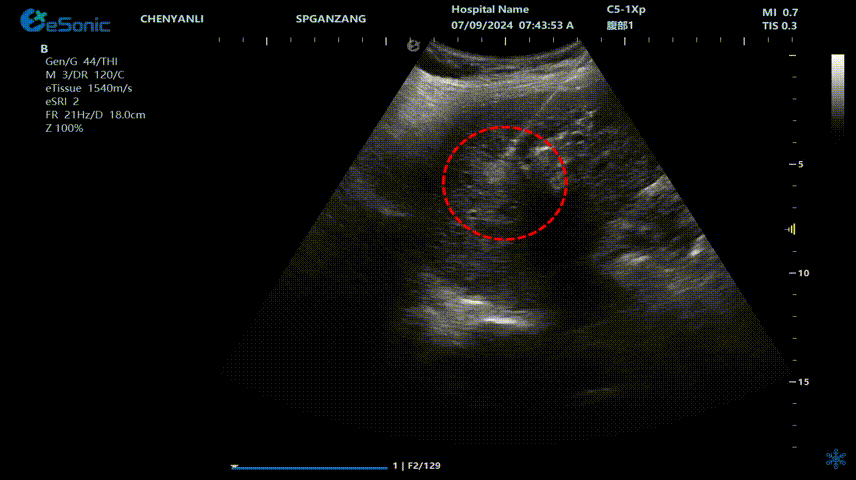

肝脏,作为人体重要的代谢和解毒器官,一旦发生肿瘤,治疗往往复杂棘手。传统的手术切除对于一些患者来说,可能因身体状况不佳、肿瘤位置特殊等因素而难以实施。而肝脏射频消融技术以其独特的微创优势脱颖而出。

一、超声实时全过程检测,较增强CT引导更快捷,无辐射,治疗过程中随时可以根据实际情况微调方案最大限度的保证了安全和彻底。

董刚教授评价:“Needle TS将射频消融从'经验操作'升级为'精准导航',尤其结合肝肿瘤、甲乳结节等复杂病例,真正实现了微创不微效!”